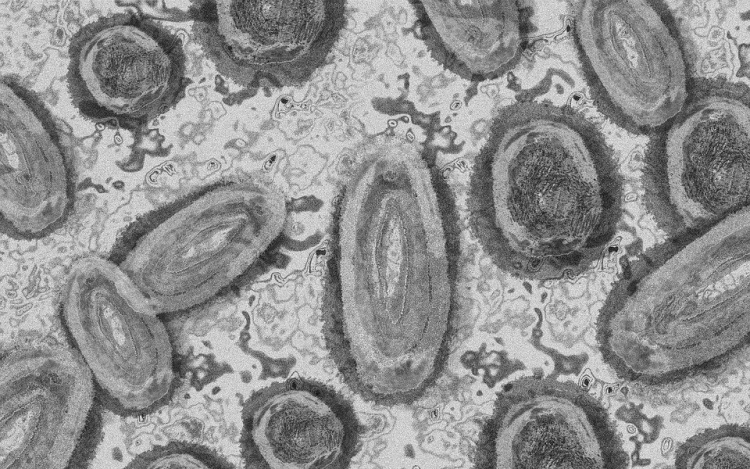

Forrás: mti/illusztráció: pixabay

Tovább nőtt a majomhimlő-fertőzöttek száma Magyarországon

Újabb két embernél igazolt majomhimlő-fertőzést a Nemzeti Népegészségügyi Központ (NNK) a 33. héten - augusztus 15-től 21-ig -, ezzel 64-re nőtt a magyarországi esetek száma.

Az NNK pénteki közlése szerint a 22 és a 31 éves férfi általános állapota megfelelő, kórházi kezelés egyikük esetében sem szükséges; otthonukban tartózkodnak elkülönítve.

A területileg illetékes járványügyi hatóság valamennyi betegnél járványügyi vizsgálatot, ennek keretében kontaktkutatást végez - tették hozzá.

Az NNK korábban azt közölte, hogy a betegség általános, nem specifikus tünetekkel - lázzal, hidegrázással, izomfájdalommal, hátfájdalommal, fejfájással, fáradtsággal -, illetve a nyirokcsomók duzzanatával kezdődik, majd 1-3 nappal a bevezető tünetek után bőrkiütések jelennek meg. A kiütések sok esetben először az arcon, majd a tenyéren és a talpon fordulnak elő, de megjelenhetnek a szájnyálkahártyán, a nemi szerveken és a végbél környékén is.